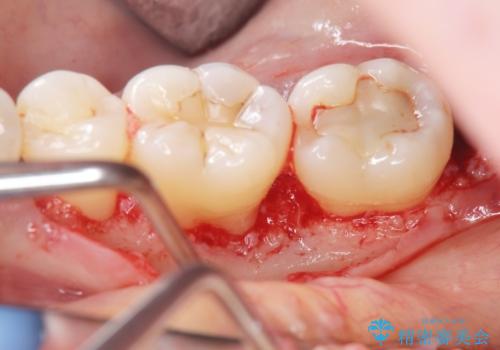

歯周病 再生治療で歯を残す

- 妊娠中に歯周病を指摘・自覚され、出産後に歯周病治療を希望され来院されました。

X線検査、歯周組織検査より歯の周囲の骨が溶ける歯周病であることがわかりました。

歯を抜かずに残せるよう、再生療法・歯周ポケット除去手術を計画します。

再生治療を行うことで、吸収した骨を再生し歯を保存できることがあります。